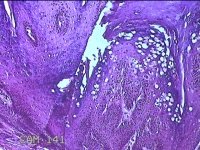

右侧拇指皮下结节

性别

男

年龄

40岁

临床诊断

皮下结节

一般病史

发现右侧拇指皮下结节1年余,无明显疼痛及不适。

标本名称

大体所见

灰白暗红色带皮肤结节0.8x0.3x0.2cm一个,表面糜烂,切开结节呈实性,切面灰白粉红色,质中。

图1